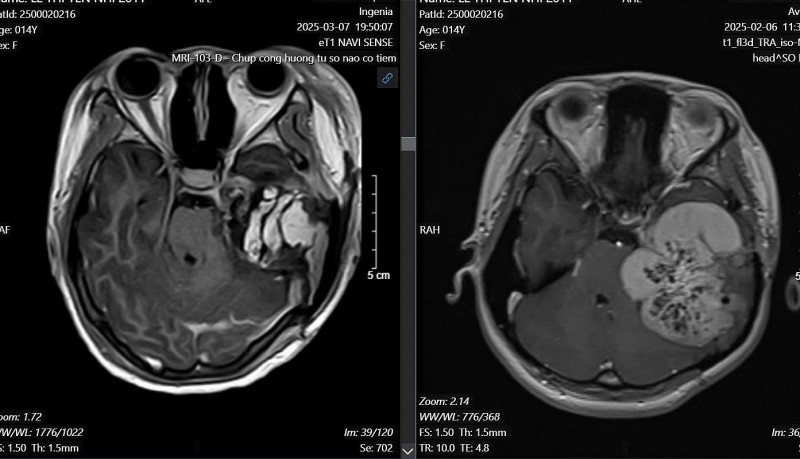

| Khối u nền sọ bên trái phát triển từ xương đá. Phim MRI trước phẫu thuật (bên phải) và sau phẫu thuật (bên trái) |

Một thiếu nữ 14 tuổi được phát hiện mắc khối u não phát triển từ nền sọ bên trái, cụ thể là từ vùng xương đá - một vị trí rất hiếm gặp. Trước đó, em đã từng trải qua hai lần phẫu thuật tại hai bệnh viện lớn ở TP HCM, tuy nhiên cả hai lần chỉ dừng lại ở bước sinh thiết, với chẩn đoán ban đầu là u máu trong xương. Sau phẫu thuật, tình trạng chảy máu tai vẫn tái diễn, khiến gia đình lo lắng và quyết định đưa em ra Hà Nội thăm khám tại Bệnh viện Hữu nghị Việt Đức vào cuối tháng 2/2025.

Ngày 6/3/2025, các bác sĩ tại Bệnh viện Hữu nghị Việt Đức, phối hợp với TS. BS Đào Trung Dũng, Phó trưởng khoa Tai Mũi Họng, Bệnh viện Bạch Mai, đã thực hiện ca đại phẫu kéo dài từ 8h sáng đến 22h đêm. Các bác sĩ đã bóc tách và cắt bỏ khoảng 90% khối u kích thước lớn (58x67x65mm), bảo tồn được dây thần kinh mặt. Ca phẫu thuật đặc biệt phức tạp do khối u xâm lấn nền sọ, phá hủy xương đá và chèn ép thân não. Bệnh nhân đã được gây mê và hồi sức tốt nhờ bác sĩ Bùi Thị Hạnh, Trung tâm gây mê và Hồi sức Ngoại Khoa, Bệnh viện Hữu nghị Việt Đức.

PGS.TS Đồng Văn Hệ - Phó Giám đốc Bệnh viện Hữu nghị Việt Đức cho biết, sự phối hợp giữa các chuyên khoa, đặc biệt là gây mê hồi sức và tai mũi họng, đã giúp bệnh nhân vượt qua ca mổ mà không để lại di chứng thần kinh nghiêm trọng. Tình trạng liệt dây thần kinh số 7 - có từ trước - không bị nặng thêm sau mổ. Kết quả giải phẫu bệnh cũng xác nhận đây là khối u túi nội dịch, đúng với chẩn đoán ban đầu của các bác sĩ.